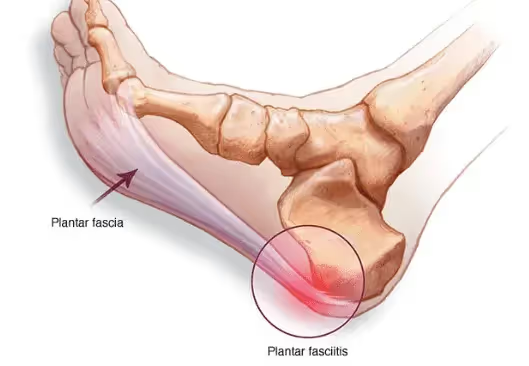

Understanding Chronic Heel Pain

Heel pain most commonly results from conditions such as chronic plantar fasciitis, Achilles tendon inflammation, or degenerative soft tissue changes. When inflammation becomes long-standing, abnormal microscopic blood vessels may develop around the painful area, continuing to stimulate pain receptors and delaying healing.

T.A.M.E. targets abnormal blood vessels responsible for ongoing inflammation and pain in chronic heel conditions, particularly plantar fasciitis.